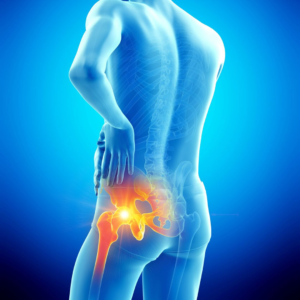

Hip Replacement

At Surecare Orthopedic Hospital, we offer advanced Hip Replacement procedures designed to relieve chronic pain, restore mobility, and improve overall quality of life. This procedure is recommended for patients with severe hip damage caused by conditions such as arthritis, fractures, or degenerative joint diseases when non-surgical treatments are no longer effective.